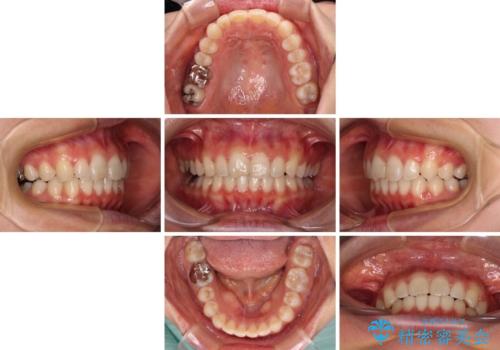

- 近々転勤の予定があるが、早めにインビザラインによる矯正治療を始めたいとのことで来院された患者様です。

上下ともにデコボコの程度は著しいものではなく、インビザラインで十分に対応可能な歯列不正でした。

インビザラインであれば来院間隔が多少長くなってもワイヤー矯正ほど問題とならないため、遠方からの通院であっても中断や転院せずに治療を行うことができます。